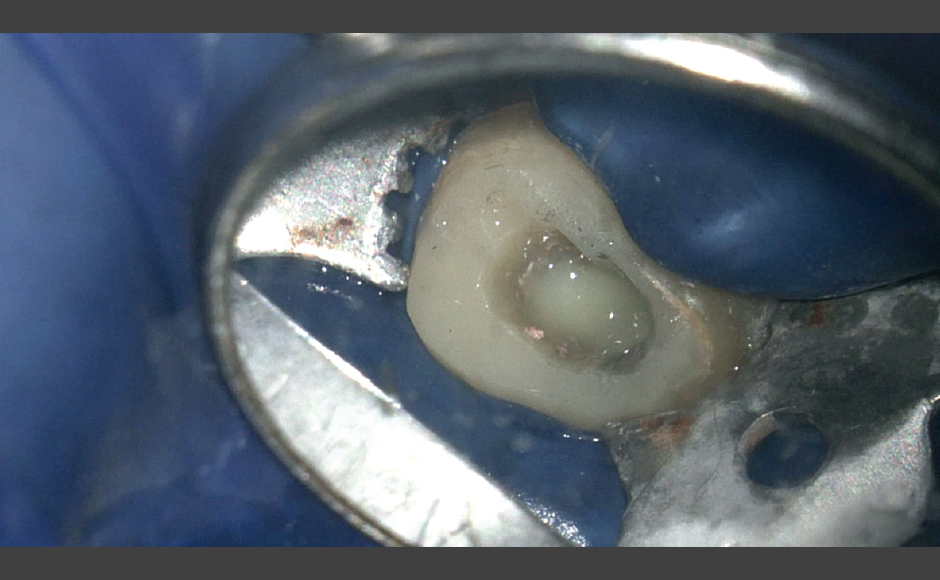

歯内療法の症例紹介 歯の保存を可能にする歯内療法の力

症例.1:穿孔を伴う根尖性歯周炎に対して非外科的歯内療法を行った症例

症例.2:外科的歯内療法を併用して根尖性歯周炎の治療を行った症例